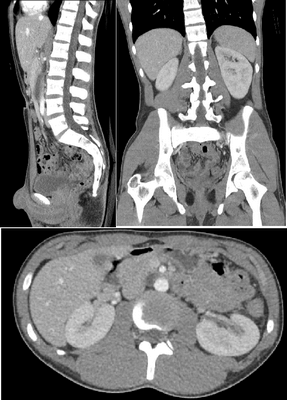

КТ може створювати детальні зображення кісток, які допомагають лікарям діагностувати переломи, кісткові інфекції та пухлини. КТ також корисна для оцінки вирівнювання кісток і суглобів, що може бути корисним при плануванні ортопедичних операцій.

КТ може створювати детальні зображення внутрішніх органів тіла, таких як печінка, нирки, підшлункова залоза та селезінка, що допомагає лікарям діагностувати переломи кісток та пухлини. Це може допомогти лікарям діагностувати широкий спектр захворювань, включаючи рак, інфекції та запалення.

КТ може створювати зображення кровоносних судин організму, що може допомогти лікарям діагностувати та контролювати такі стани, як аневризми, згустки крові та атеросклероз. КТ також може використовуватися для проведення малоінвазивних процедур, таких як ангіопластика та стентування.

КТ особливо корисна для оцінки м’яких тканин, таких як мозок, м’язи та лімфатичні вузли. КТ може допомогти лікарям діагностувати широкий спектр захворювань, включаючи пухлини, інфекції та запалення.

КТ може виявити широкий спектр патологій, включаючи пухлини, інфекції та кісти. КТ-сканування також корисне для оцінки розміру та розташування цих аномалій, що може бути корисним при плануванні лікування.